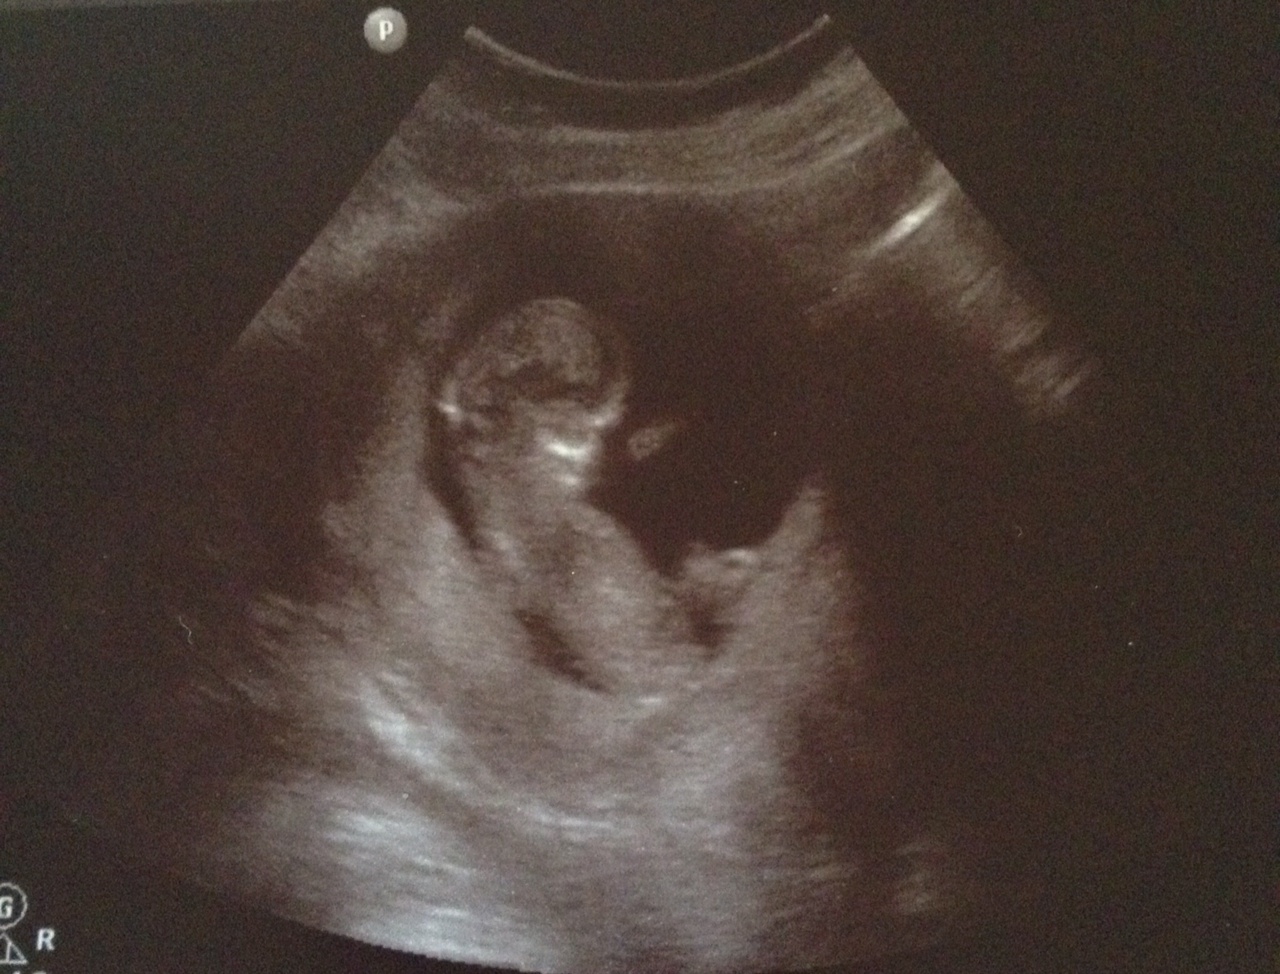

This was 12+6 gestation. All guesses welcome, I'm intriguedAttachment 18242 - thank you!

You can just about make out the nub there but the end is rather blurry. Overall it looks relatively flat and possibly extends past the bum making it more girly but if there is a bump on the top then obviously it would look more boyish. Overall I have to say I am still 50/50. Some people have a theory that more curled up babies are girly but the curve in the spine can make a nub appear flatter than it really is. Xx

That skull looks girly but hard to tell about the nub. Are you in the UK? Xx